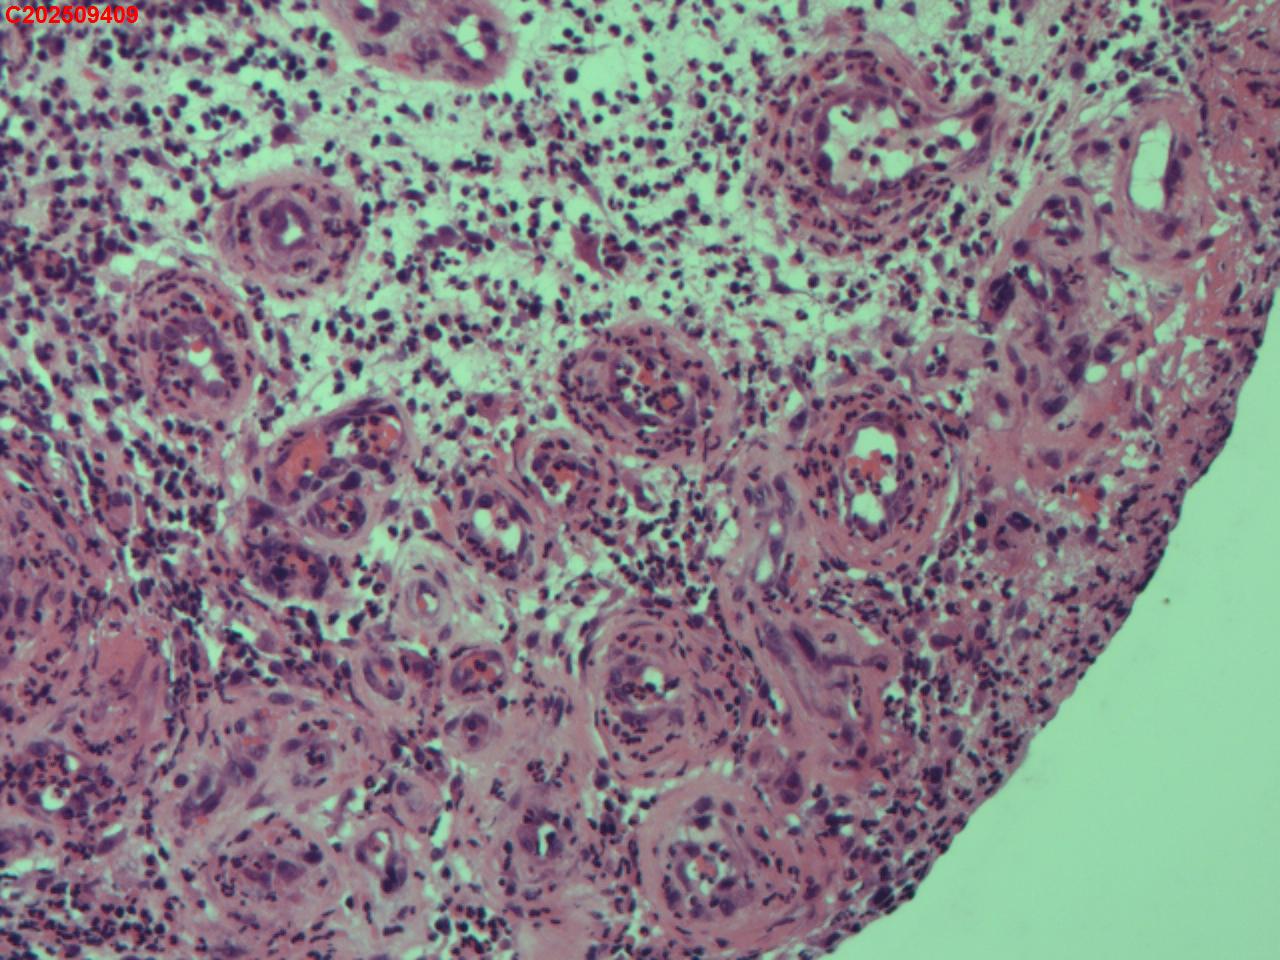

性别年龄62岁临床诊断社区获得性肺炎,肺占位性病变带除外

一般病史胸部CT:双肺可见多发斑片状、结节状高密度影,右肺上叶及左肺下叶病灶内见多发空洞,右侧少量胸腔积液。

标本名称纤支镜咬检

大体所见纤支镜:气管通畅,隆突锐利。右肺主支气管通畅,右肺上叶见少量痰液,负压吸引后见上叶开口干酪坏死物质附着,上叶各段级支气管通畅未见新生物及坏死物质,中叶、下叶背段支气管通畅,下叶基底段见新生物阻塞气道,粘膜无充血。左肺主支气管、上叶、下叶及各段级支气管通畅,粘膜无充血,未见新生物及坏死物。

考虑:支气管炎性息肉